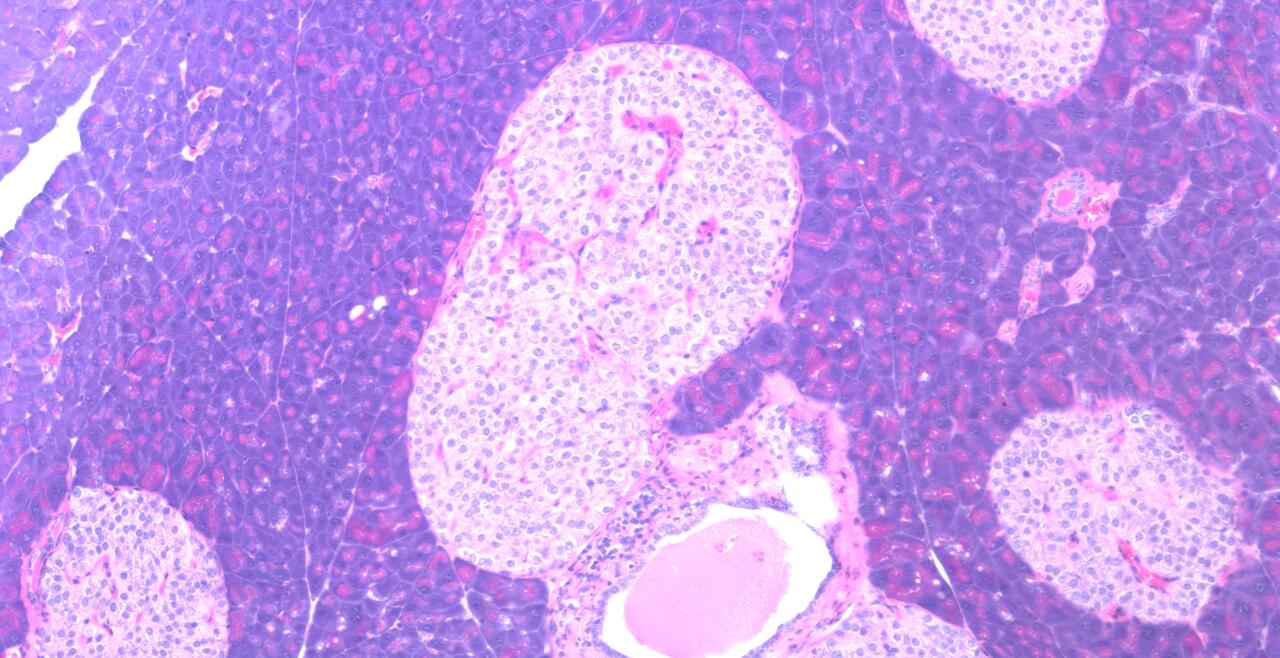

Images from research in the Banks Lab